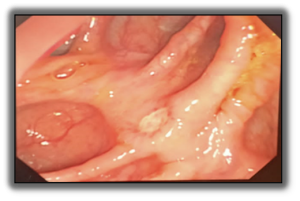

4 / 5

4. A 44-year-old male presents with a 5-year history of chronic diarrhea and recent right lower-quadrant abdominal pain. Colonoscopy reveals the appearance shown in the image, with multiple elongated superficial ulcers and intervening normal mucosa. Which of the following is the most likely diagnosis?